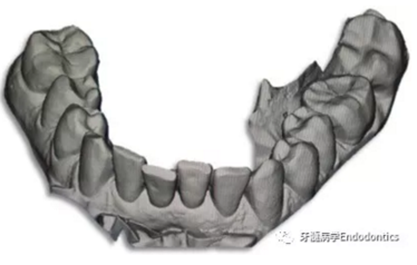

31、41叩痛明顯,牙冠變色(圖1)。溫度和牙髓電活力測(cè)試無反應(yīng)。兩張從不同角度拍攝的x線片顯示,相對(duì)于側(cè)切牙,雙側(cè)下中切牙都有嚴(yán)重的根管鈣化(圖2)。41有明顯根尖周暗影,31根尖周暗影不明顯。為進(jìn)一步證實(shí)31是否存在根尖周病變,同時(shí)精細(xì)觀察31、41的復(fù)雜結(jié)構(gòu),根據(jù)歐洲牙髓病學(xué)會(huì)CBCT應(yīng)用指南(2014),對(duì)患牙拍攝小視野、高分辨率CBCT。CBCT影像證實(shí)31、41均伴有根尖周炎和嚴(yán)重的根管鈣化(圖3)。距離根尖4mm可見根管影像。 由于患牙根管解剖結(jié)構(gòu)較為復(fù)雜,筆者決定使用特殊設(shè)計(jì)的微型鉆頭(直徑0.85mm)進(jìn)行“數(shù)字化導(dǎo)航牙髓治療”。 因此對(duì)下頜進(jìn)行口內(nèi)掃描(圖4)。用coDiagnostixTM軟件(Dental Wings Inc.,Montreal,Canada)將CBCT和口內(nèi)掃描的數(shù)據(jù)進(jìn)行處理,該軟件主要用于引導(dǎo)種植。通過該軟件對(duì)兩個(gè)掃描圖像進(jìn)行疊加后,虛擬鉆頭尖端沿牙長(zhǎng)軸對(duì)準(zhǔn)根管下段可見部分(圖5)。三維檢查虛擬鉆的正確位置。

圖4.下頜牙口內(nèi)表面掃描的表面鑲嵌語言(stl-)數(shù)據(jù)。